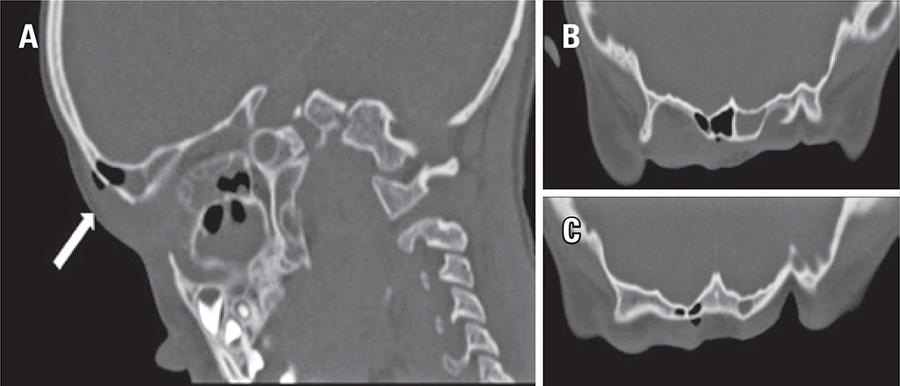

A 5-year-old boy with previous history of frontal sinus fracture, 2 years ago, with conservative treatment and no current surgical follow-up. Upon admission, he had sudden onset of fever, severe swelling over the right eyelid and supraciliary region, and painful ocular movement. Physical examination showed no other alterations, therefore, excluding neurological compromise. Laboratory tests revealed raised inflammatory markers. For staging the extent of inflammation and exclude intracranial complications a computed tomography scan of the head and orbits was performed and revealed right frontal and periorbital swelling extending to postseptal area without optic nerve involvement. In addition, we observed subcutaneous emphysema around a break in the continuity of the anterior wall of frontal sinus table and a process of acute pansinusitis with air-fluid levels involving maxillary, ethmoid, sphenoid and frontal sinuses; there was no abscess formation. We admitted the diagnosis of orbital cellulitis and facial subcutaneous emphysema due to pansinusitis. Facial subcutaneous emphysema has been reported as an acute complication of head trauma.(–)However, in this case, it was caused by a late complication of past bone fracture, probably triggered by an acute process of frontal sinusitis, which is a rare complication.